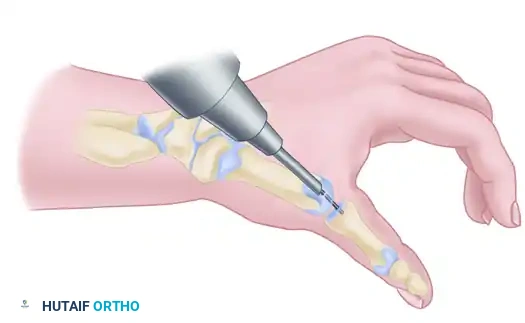

2. Joint Preparation: The Cup-and-Cone Technique

Achieving a high union rate requires maximizing the cancellous bone contact area. The "cup-and-cone" technique is highly recommended as it provides intrinsic stability and allows for fine-tuning of the thumb position before definitive fixation.

- Metacarpal Preparation (The Cone): Use a rongeur and an air-driven burr to remove the remaining articular cartilage and dense subchondral bone from the base of the first metacarpal. Shape the base into a convex, cone-shaped surface of healthy, bleeding cancellous bone.

- Trapezial Preparation (The Cup): Use a high-speed burr, curet, and small osteotomes to shape the distal articular surface of the trapezium into a concave cup configuration. The radius of curvature must match the metacarpal cone perfectly.

Appose the prepared bone surfaces and assess the fit. The cup-and-cone geometry allows the surgeon to rotate and angulate the metacarpal into the perfect functional position without losing bony contact.